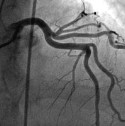

Neuer deutscher Herzbericht

Sterblichkeit nimmt weiter ab, immer bessere Versorgung

„In Deutschland geht die Sterblichkeit in Folge von Herzerkrankungen weiter zurück. Ursache ist die immer bessere kardiologische Versorgung, die inzwischen ein ausgezeichnetes Niveau erreicht hat. Hier gibt es noch regionale Unterschiede, an denen gearbeitet werden muss. Auch alte Menschen profitieren immer mehr von den Entwicklungen der modernen Herz-Medizin“. So fasst DGK-Präsident Professor Dr. Christian Hamm (Gießen) die zentralen Aussagen des aktuellen Deutschen Herzberichts zusammen, der heute in Berlin vorgestellt wurde. „Diese sektorenübergreifende Versorgungsanalyse, die bereits zum 25. Mal durchgeführt wurde, trägt sehr viel zum Verständnis der Trends in der herzmedizinischen Versorgung in Deutschland bei und liefert wesentliche Beiträge zu einer noch besseren Versorgungs-Planung.“